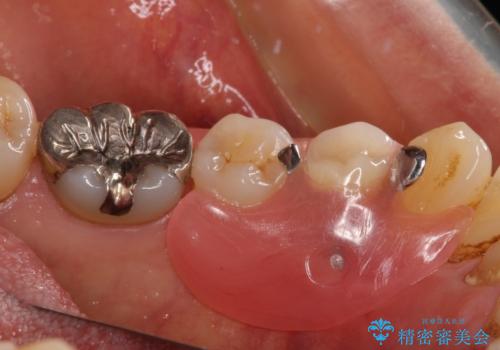

インプラント治療をお勧めしましたが、取り扱いや手入れが煩雑でも良いとのことで、可撤性義歯(入れ歯)にて補綴治療を行うこととしました。

近年の入れ歯は、クラスプという金属のバネのない、ノンクラスプデンチャーが主流となってきており、金属がほとんど使用されなくなっています。しかし、両隣の歯にぶら下がる部分には金属によるフック(レスト)を用いることが、咬み合わせや周辺の歯の安定に大きく寄与するため、今回もレストのみに金属を使用したノンクラスプデンチャーを製作しました。